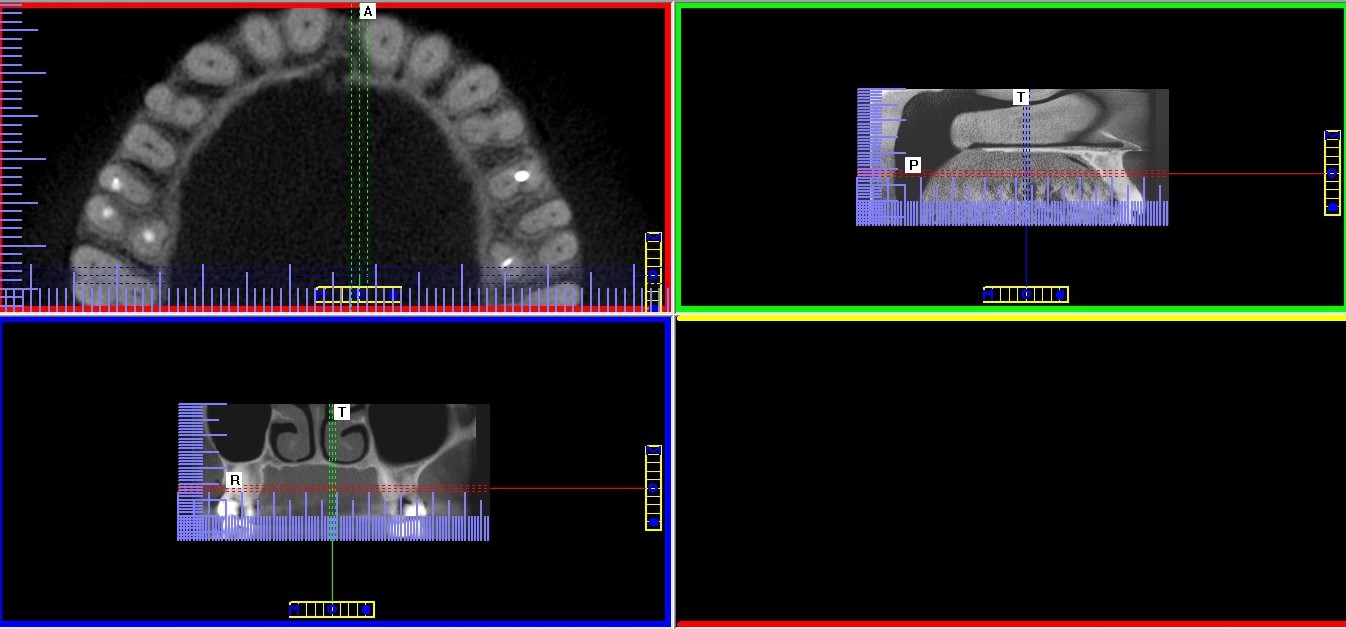

– Obrazowanie 3D, czyli tomografia – w endodoncji najczęściej wykorzystuje się tomografię komputerową wiązki stożkowej (cone bean computed tomography – CBCT) o tak zwanym małym polu obrazowania. Dzięki temu można uzyskać wyraźne, szczegółowe skany zęba przy stosunkowo małej dawce promieniowania i zachować zasadę ALARA (as low as reasonably achievable) dotyczącą ochrony radiologicznej. Według tej zasady dawka promieniowania musi być utrzymana na możliwie najniższym poziomie, w taki jednak sposób, aby nie ograniczać możliwości diagnostycznych w trakcie leczenia (6). Dzięki temu, że na skanach tomografii komputerowej uzyskujemy wirtualne przekroje w płaszczyźnie czołowej, strzałkowej i osiowej można dokładnie prześledzić budowę i ewentualne krzywizny kanału. Tomogramy pozwalają również wykryć kanały dodatkowe i znaleźć przyczyny ewentualnych niepowodzeń pierwotnego leczenia kanałowego (ryc. 5‑8). Gopikrishna i wsp. dzięki zastosowaniu tomografii komputerowej odkryli nietypową budowę zęba trzonowego górnego z dwoma kanałami podniebiennymi i tylko jednym kanałem policzkowym (7). W innej publikacji opisano przypadek pierwszego zęba trzonowego szczęki z pięcioma kanałami, w tym dwoma kanałami podniebiennymi (8). W badaniu Huumonen i wsp. dzięki wykorzystaniu tomografii stwierdzono obecność kanału dodatkowego (MB2) w 30 z 39 ocenianych zębów trzonowych szczęki. Jednocześnie zaobserwowano, że aż 27 kanałów dodatkowych nie zostało wykrytych, co spowodowało powstanie zmian zapalnych w tkankach okołowierzchołkowych w przypadku 22 z 27 nieleczonych kanałów (9).

Ryc. 5. Tomogram szczęki. Widoczny poprzeczny, „wirtualny” przekrój przez korzeń zęba 25 w około połowie jego długości: nieleczony kanał podniebienny, kanał policzkowy wypełniony.

Źródło: Olczak K. Wykorzystanie tomografii wolumetrycznej podczas ponownego leczenia kanałowego drugiego zęba przedtrzonowego szczęki. Mag Stomatol. 2019; 9: 23.

Ryc. 6. Tomogram szczęki. Widoczne „wirtualne” przekroje przez korzeń zęba 25 w trzech płaszczyznach, widoczne zmiany zapalne w tkankach okołowierzchołkowych i niewielka ilość uszczelniacza poza wierzchołkiem.